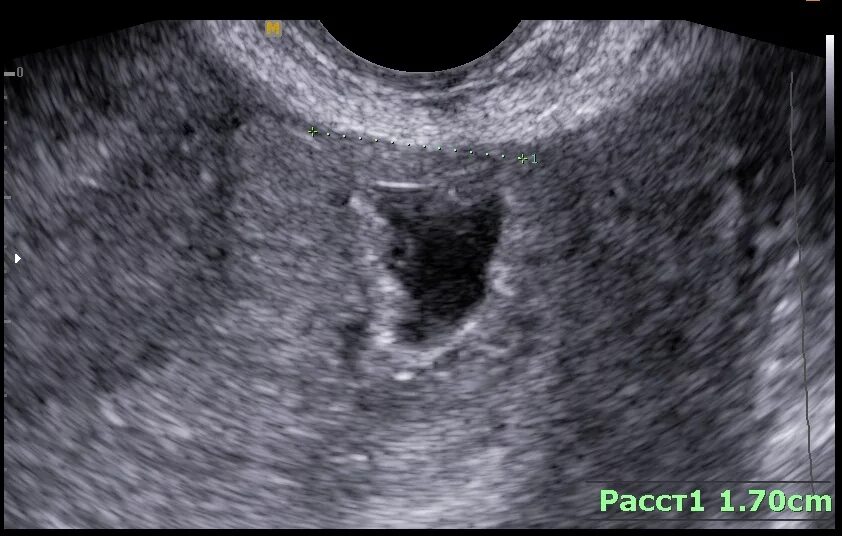

Эмбрион не прикрепился к матке причины